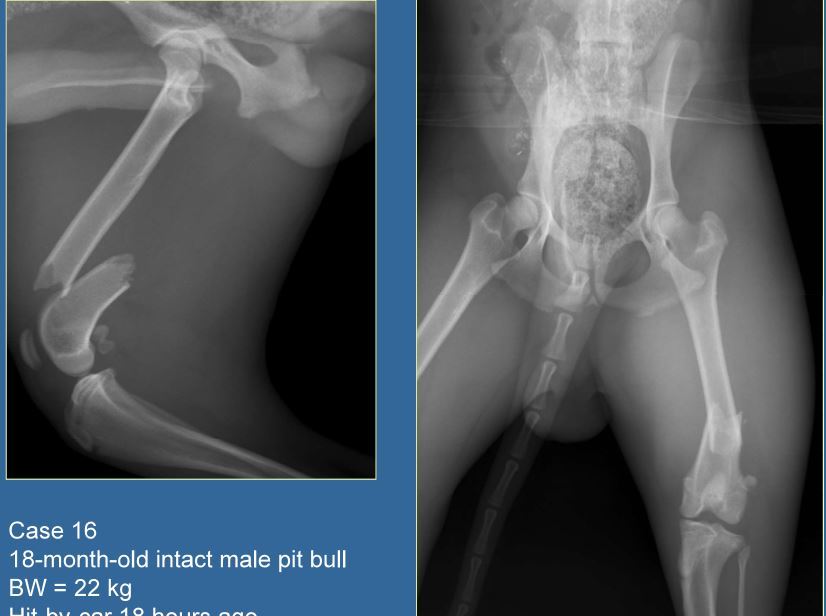

18 month old M pitbull, 22kg

A

Simple transverse fracture of the distal diaphysis of the femur

Fx score= 10

Repair= ESF + IM pin

IM pin + cerclage wire C/O’d on transverse fx